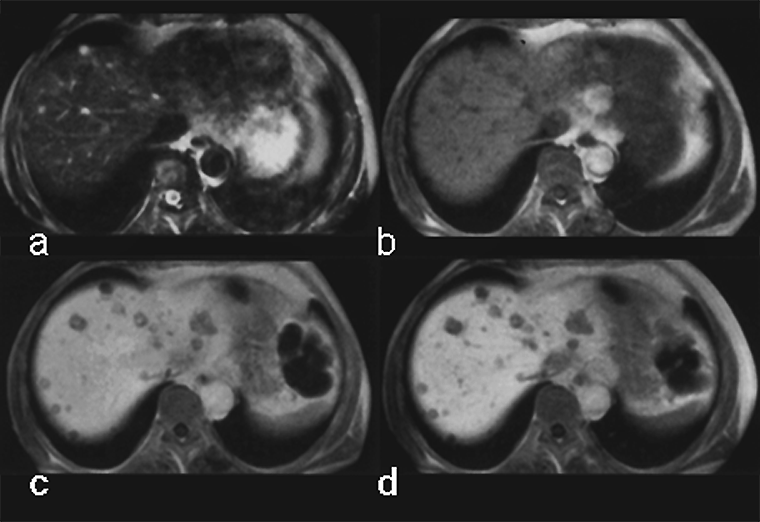

Figura 13-13:

Focal nodular hyperplasia (FNH) of the liver. Dynamic en­hance­ment with Gd-DOTA; first high­light­ing of the arterial vessels, then strong en­hance­ment of the tumor during the early phase of ar­te­rial en­hance­ment; followed by the depiction of the veins. Timescale approximately 90 seconds.

Although the chemical composition of Gd-BOPTA appears similar to that of the extracellular gadolinium agents, it combines both extracellular and liver-targeted properties, because some 5% of it is excreted through the liver, as is shown in this case of multiple metastases (Figure 13-14).

Figura 13-14:

Gadolinium-BOPTA in liver metastases of a pancreatic tumor.

(a) plain T1-weighted GRE sequence; (b) plain T2-weighted GRE sequence; (c) enhanced T1-weighted GRE sequence 40 minutes after injection; (d) T1-weighted GRE sequence 90 minutes after injection.